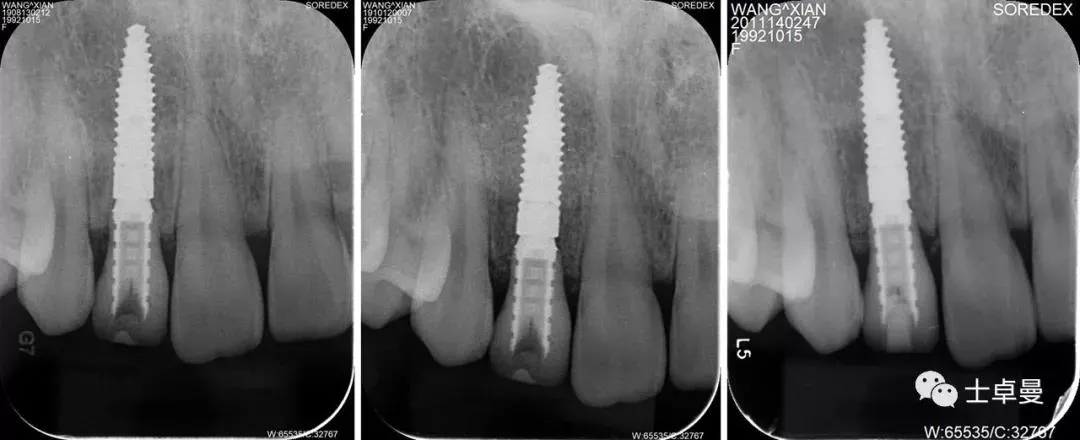

·        根尖片显示临时基台就位良好,无骨阻挡;

每次复查的根尖片

术后一年的CBCT

术后三年的CBCT

不同时期CBCT截图